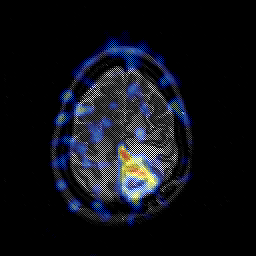

Glioblastoma multiforme overlay -- Slice #42